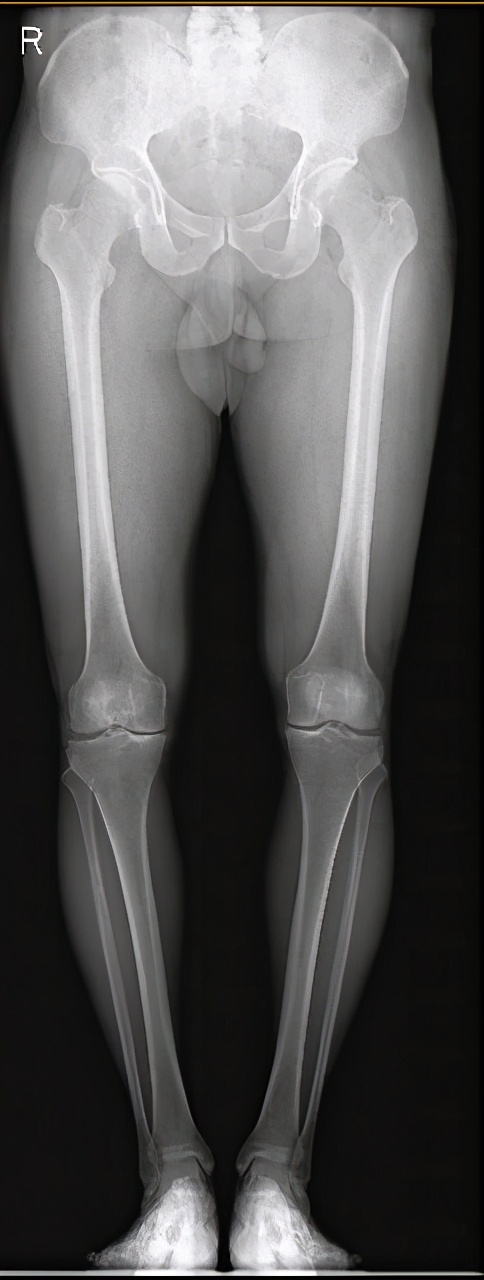

图5 胫骨高位截骨手术前x片

图5 胫骨高位截骨手术后x片。

图5 :术前x片显示左膝关节内侧狭窄,膝关节(胫骨)内翻;术后下肢力线向膝关节外侧转移,膝关节内翻得到纠正,改善了膝关节内侧受力,缓解内侧疼痛